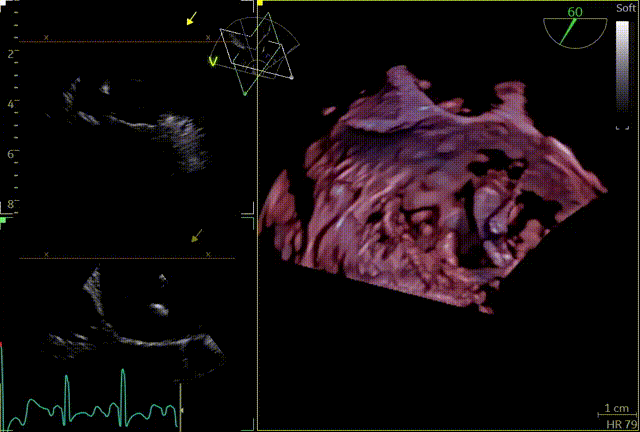

3D

3D带彩